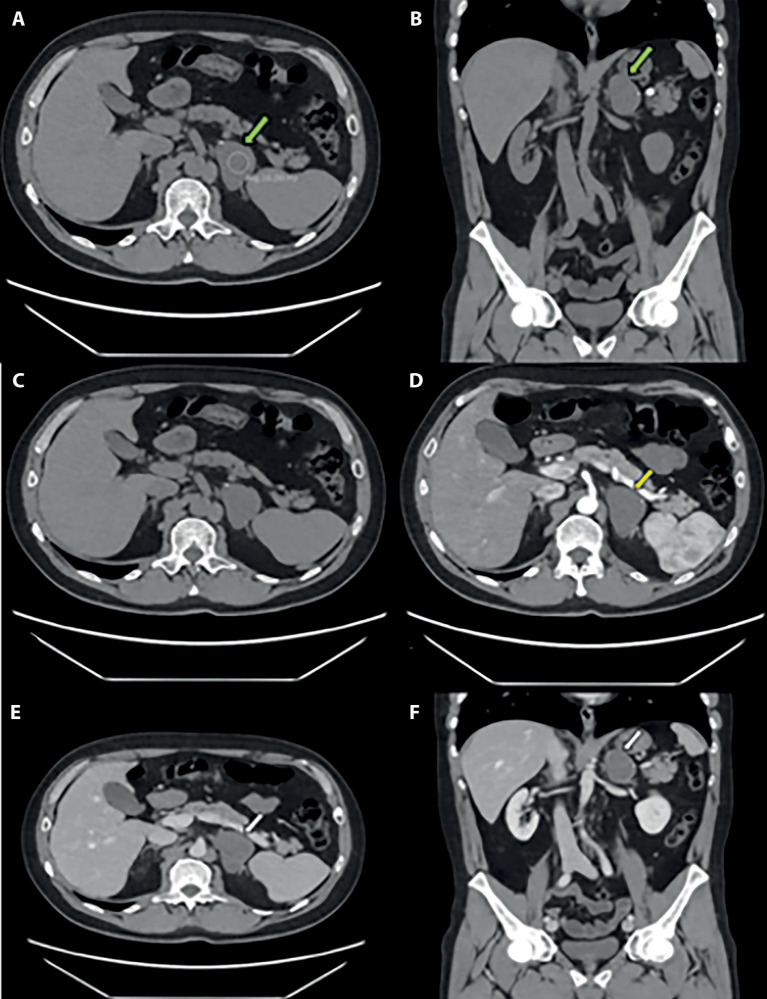

A 53-year-old man complaining of pain in the right hypochondrium underwent an abdominal ultrasound that showed a left adrenal lesion. Further instrumental investigations (CT and MRI, both with contrast medium) were performed which diagnosed an adrenal ganglioneuroma, confirmed by the histological examination. The patient also underwent an endocrinological examination. The treatment was surgical and consisted of an adrenalectomy through video-laparoscopic access. Adrenal ganglioneuromas are rare tumors but well described and known in the literature. For this reason, this case report has primarily an educational purpose: the totality of the data collected (clinical, laboratoristic, instrumental, and histopathological) constituted a multidisciplinary case, with the focus on imaging.